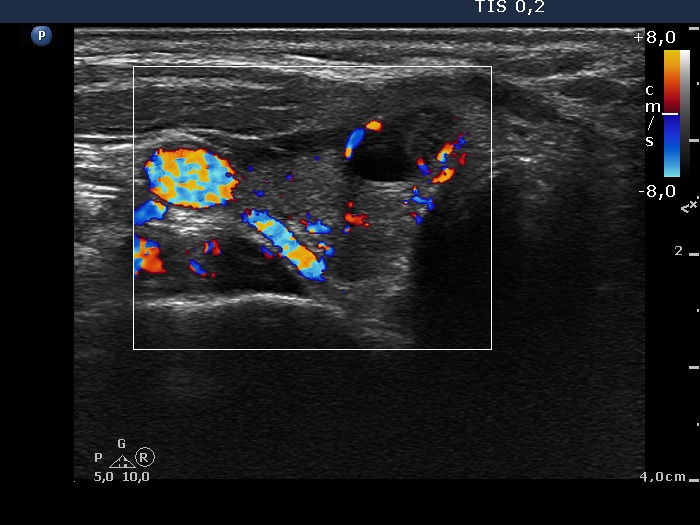

Initial examination (1st and 2nd rows of images):

Ultrasonography: there were multiple hypoechogenic areas with ill-defined borders in both lobes, primarily in the right one. The vascularization was decreased.